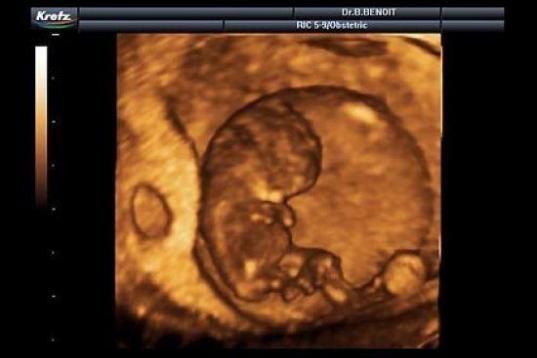

En esta galería puedes ver en fotos como es el desarrollo de un feto de semana en semana:

Desarrollo del feto, en fotos